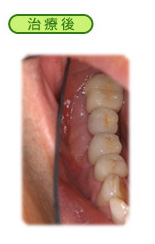

歯周病

以前は「不治の病」とさえ言われていた歯周病も、現在では進行を阻止することが可能となり、状況によっては元の健康な状態に戻すこと(再生療法)さえ出来るようになってきました。

われわれは、常に治療効果の高い新しい技術を習得するために、毎年数回は国内外の専門分野の学会(米国歯周病学会、日本歯周病学会、日本臨床歯周病学会など)や研修会(米国先端歯科医療研修会:IADSなど)に参加し、われわれの治療例の発表をしています。

そして、1本でも多くの歯を保存するよう常に努力しています。